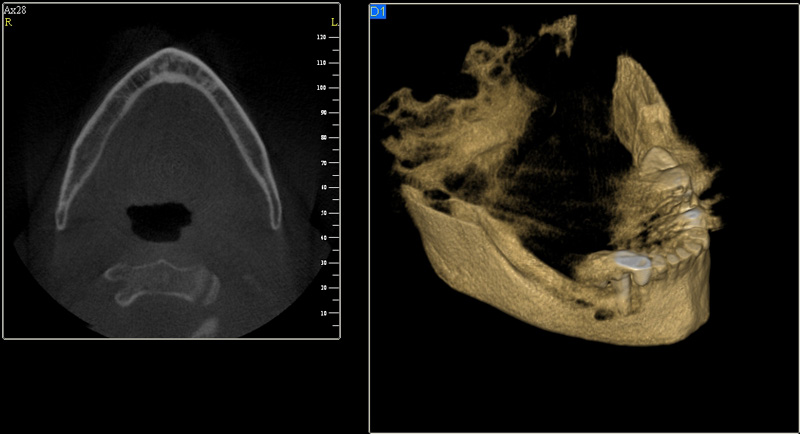

Tyto postupy nám umožní doplnit chybějící množství kosti v čelistech pacienta i zlepšit kvalitu kosti. Většinou se setkáváme s omezenou nabídkou kostní tkáně díky resorpčním (úbytkovým) procesům způsobených věkem či vytržením zubu, přítomností anatomických struktur jako je čelistní dutina, nervový kanál nebo patologických či poúrazových stavů - cysty, zlomeniny.

Při ztrátě molárů a premolárů v horní čelisti a jejich náhradě implantáty se často setkáváme s nedostatečnou vertikální nabídkou kosti pod čelistní dutinou, často doprovázenou i nedostatečnou horizontální nabídkou a sníženou kvalitou kosti

(v oblasti 2. premoláru v 50%, v oblasti moláru až v 80% případů nedostatečná kostní nabídka)

Jedná se o vyzvednutí membrány, která čelistní dutinu vystýlá, pod vyzvednutou membránou vznikne kapsa, kam se umístí augmentační materiál, do kterého se zavedou implantáty.